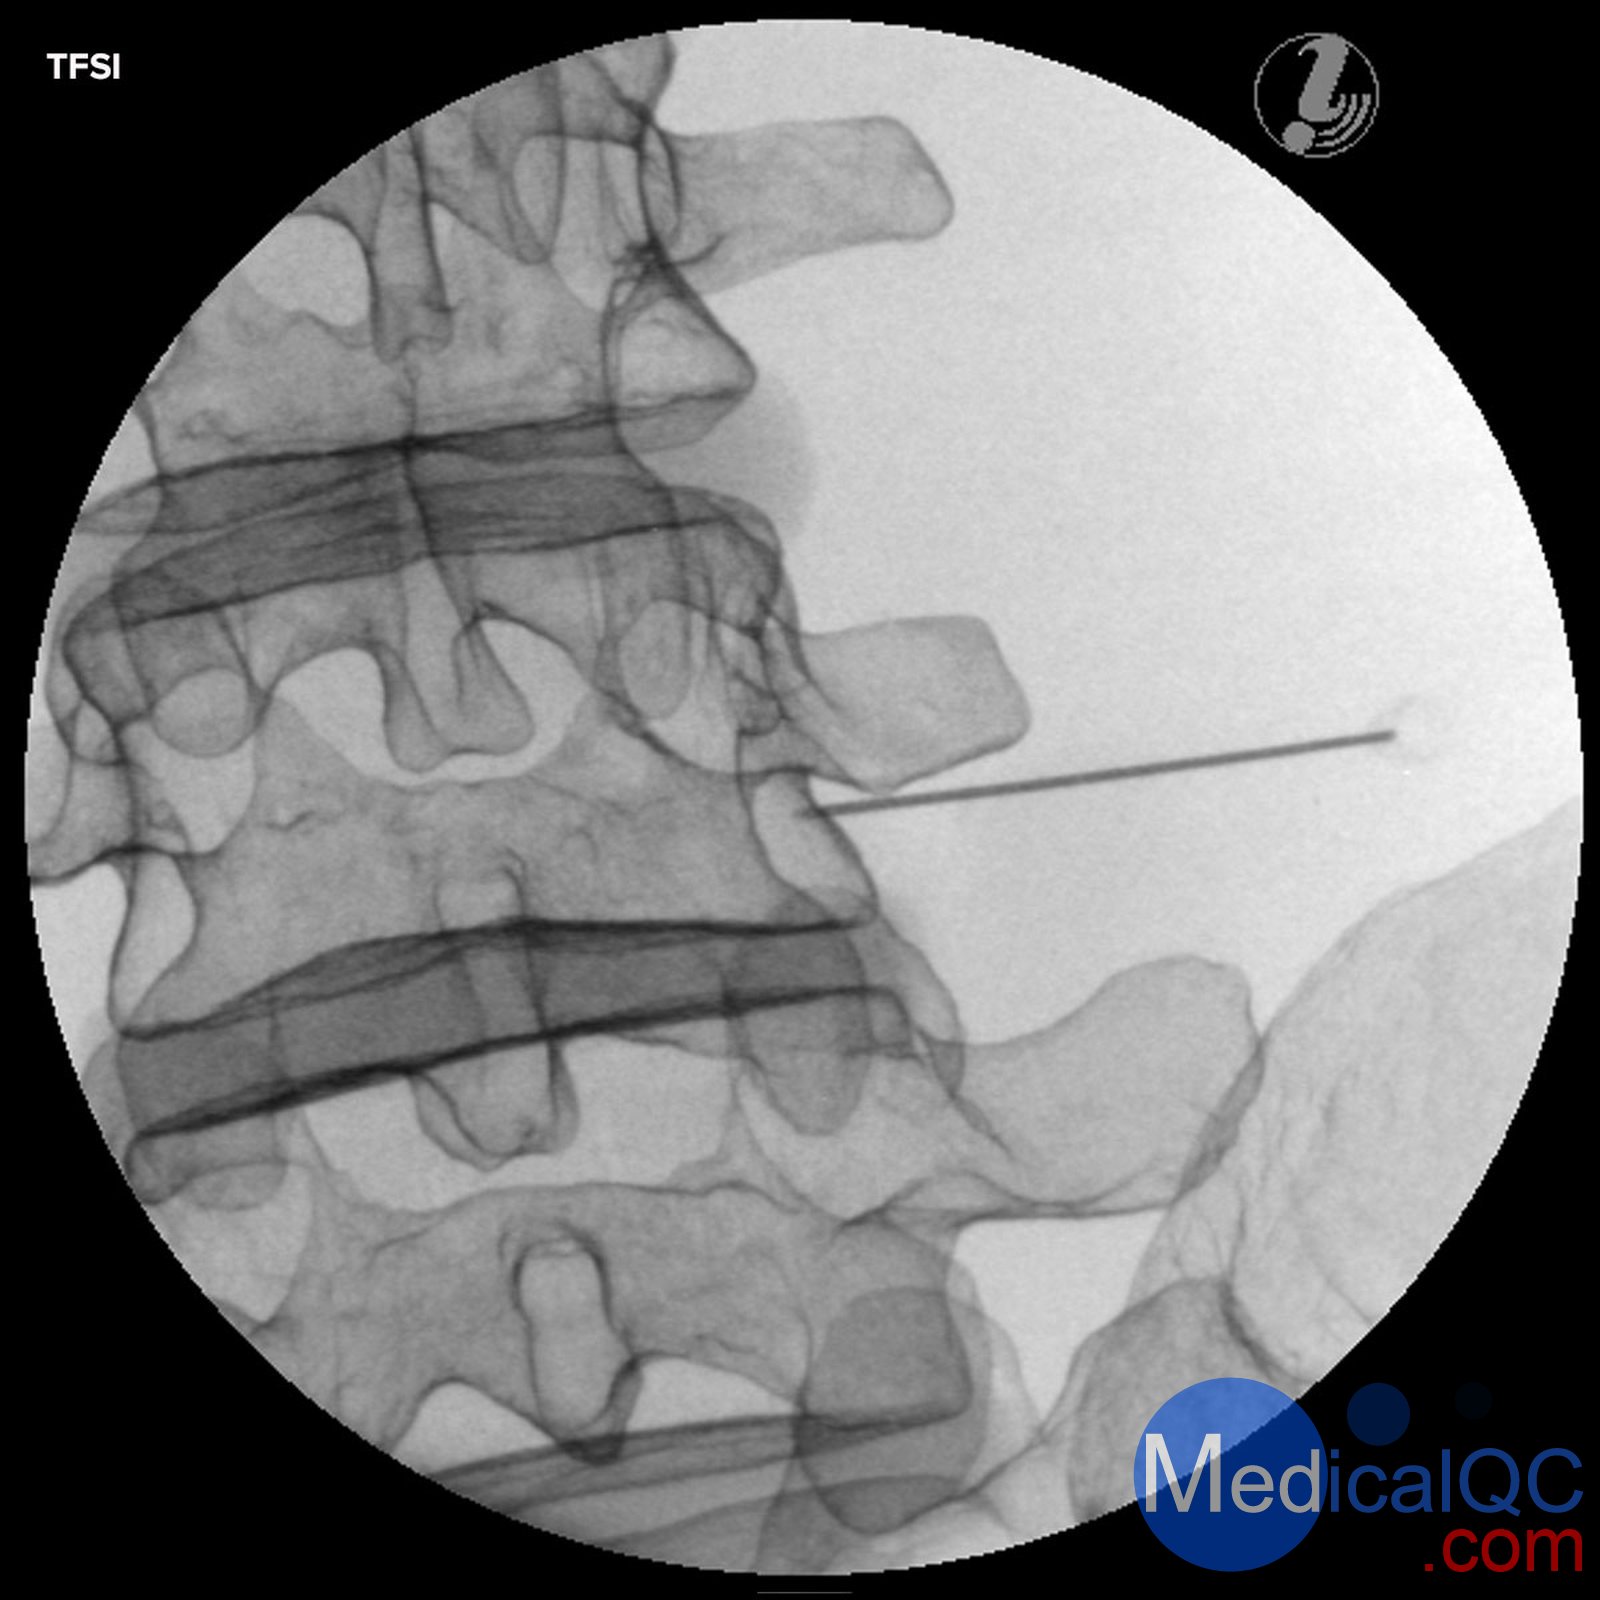

經(jīng)顱內(nèi)硬膜外類固醇注射(TFSI)

Image Guided Lumbar Spinal Injection Trainer

Improve outcomes of spine interventions with standardized image guided injection training

The Image Guided Lumbar Spinal Injection Trainer enables trainees to develop a three-dimensional understanding of the procedures for successful spine interventions. They will learn to correlate imaging with the lumbar spinal anatomy relevant to interventional pain procedures, to identify the target tissue and vulnerable structures using imaging and anatomic inspection, and to apply best practices to ensure patient safety during the interventional spine procedures.

Using the Spinal Injection Trainer is an economic alternative for imaging techniques courses on cadavers and offers the instructors a reliable, standardized patient simulation always ready to use:

Life-like radiopacity for realistic x-Ray images

Realistic injection haptics

Anatomically accurate bone structure

Visually identifiable landmarks

The following image guided spinal interventions can be trained on the simulator:

Transforaminal Epidural Steroid Injections (TFSI)